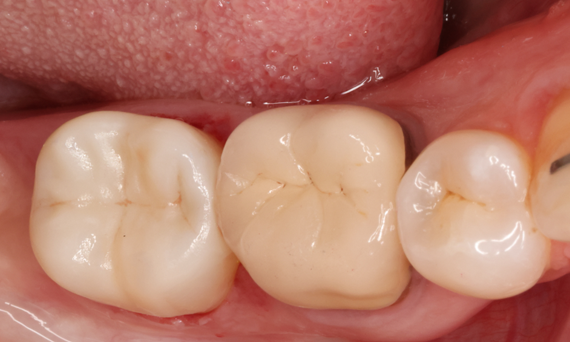

Second lower right molar in 90 minutes

A CEREC Tessera onlay

A 20-year-old female patient had endodontic treatment of her lower right 2nd molar. A chairside onlay was fabricated from the new high-strength ceramic CEREC Tessera ALD.

Before: Pre-operative clinical scenario after endodontic therapy.

After: 1 month after the CEREC Tessera onlay was bonded.